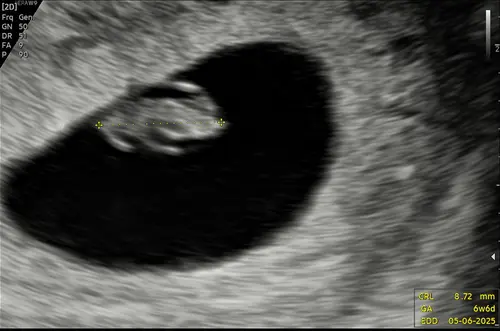

Ik zou nog een echo aanvragen. Zo zagen al mijn echo's er namelijk uit rond dat termijn. En heb 5 gezonde kindjes rondlopen en een 6e gezonde onderweg. Absoluut nog geen medicijnen nemen hoor !!!! We duimen allemaal voor je dat het allemaal goed zit en goed komt 鉂わ笍馃グ

De gynaecoloog gaat altijd eerst een inwendige echo maken om te controleren of er echt geen hartactiviteit zichtbaar is voordat er medicatie wordt voorgeschreven. Hier zijn ze heel nauwkeurig in. Bij mij werd het zelfs nog door een tweede gynaecoloog gecontroleerd. Heel veel sterkte gewenst en ik hoop met je mee op een wonder.

Das het probleem uitwendig werd er wel wat gezien en een kloppend hartje en inwendig niks. Dus als de gynaecoloog ook inwendig gaat doen zal hij ook niks zien. De meest grove fout die heel veel gemaakt word......uitwendig zien we niks....

Ik heb nu tot twee keer toe gehad dat ze inwendig geen drol zagen geheel zwart beeld bij de 7/8 weken en uitwendig een keurig mooi kloppend hartje.

Toch nog voor de zekerheid uitwendig en boem: kloppend hartje, alles.

Ik heb in december een missed abortion gehad. Doorverwezen naar de gynaecoloog en die heeft uitwendig en inwendig een echo gemaakt. Hij is wel 20 min bezig geweest om zeker ervan te zijn dat er niks over het hoofd werd gezien voordat ik de medicatie zou krijgen.